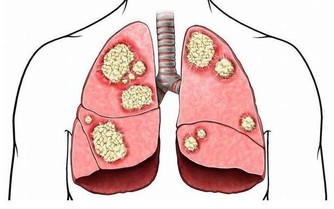

我們知道,腎臟的一個主要功能就是排水,尿液就是從這裡產生的,

一旦腎臟的排水功能出現了問題,喝水的時候就需要注意一些了。

哪些腎病患者需要控制飲水呢?是那些腎臟排水功能受損的患者。

臨床上認為,“少尿”的標準是每天少於400ml,

“無尿”的標準是每天少於100ml,這些腎病患者是需要控制飲水的。